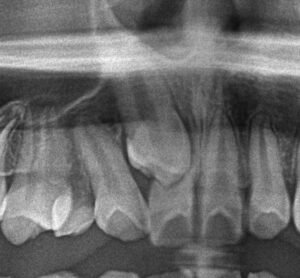

犬歯が骨の中に埋まっており、かつ右上一番目の歯(中切歯)の根を病的に溶かしてしまっている状態でした(下写真参照)。ここまで歯根吸収が起きていると、歯根が溶けてしまった中切歯は予後不良と判断し、抜歯の対象となります。上顎前突(いわゆる出っ歯)も認めるため、左上も抜歯して上下の前歯を後退させる方針としました。下顎前歯に先天性欠如を認めたため、下顎は抜歯を行いませんでした。歯列矯正を行うことで、きれいな歯並びとかみ合わせを獲得しています。右上に関しては犬歯の先端は尖った形状をしているため、左上中切歯との並びが不揃いになることから、右上犬歯にはレジンと呼ばれる歯科用材料で隣の歯の形に似せるように形態修正を施しています。下顎前歯が1本先天性欠如であり、上下の前歯の本数がそれぞれ4本と3本で異なっているため、上下歯列正中の仕上がりはご覧の通り、上顎の正中が下顎前歯の中央に一致する形となります。